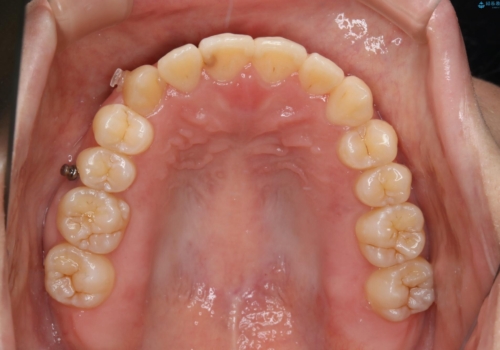

八重歯とクロスバイト:インビザライン治療

- 八重歯が気になるとの事でご相談にいらした方です。

インビザラインで綺麗に並べました。

気になっていた八重歯が綺麗になって大変喜んでいただけました。